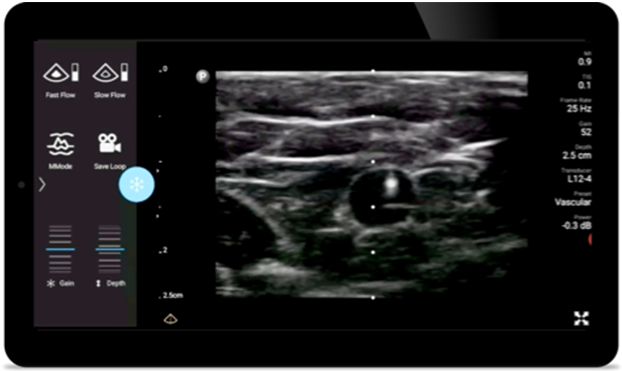

Reduce complications

in needle guided procedures

Lumify handheld ultrasound for anesthesiology helps you clearly visualize border definition with your needle placement, surrounding nerves, vessels and fascial planes.

Lumify helps you clearly visualize needle placement, surrounding nerves, vessels and fascial planes.